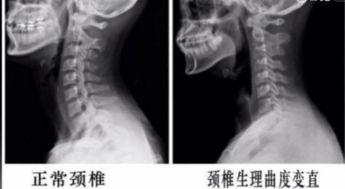

你有没有看过那种颈椎头手对抗的视频?是不是觉得既好奇...